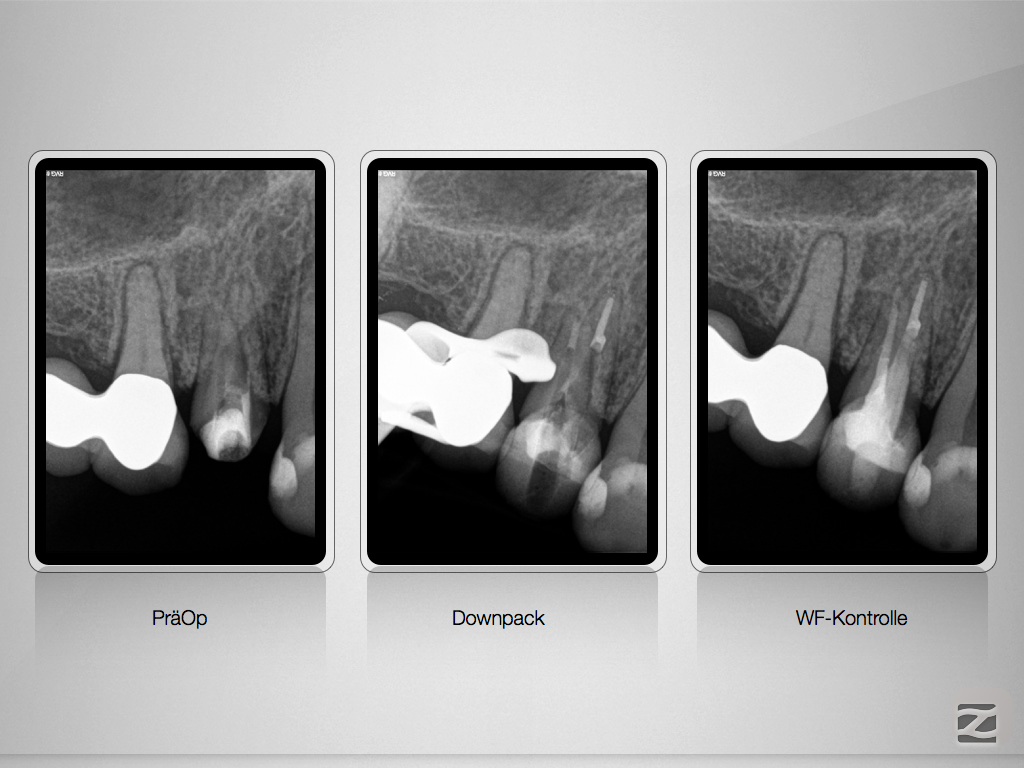

Immer schön skeptisch bleiben 3